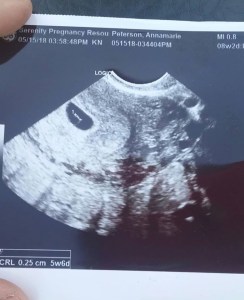

The sweet nurse couldn’t find a baby either, until she switched from using a doppler to a transvaginal wand. Baby was tiny, microscopic. 5 weeks, 6 days, she said. I mentally corrected it to 5 weeks and 4 days, because I knew when I’d ovulated, but close enough. We were so relieved. Maybe this was really happening after all.